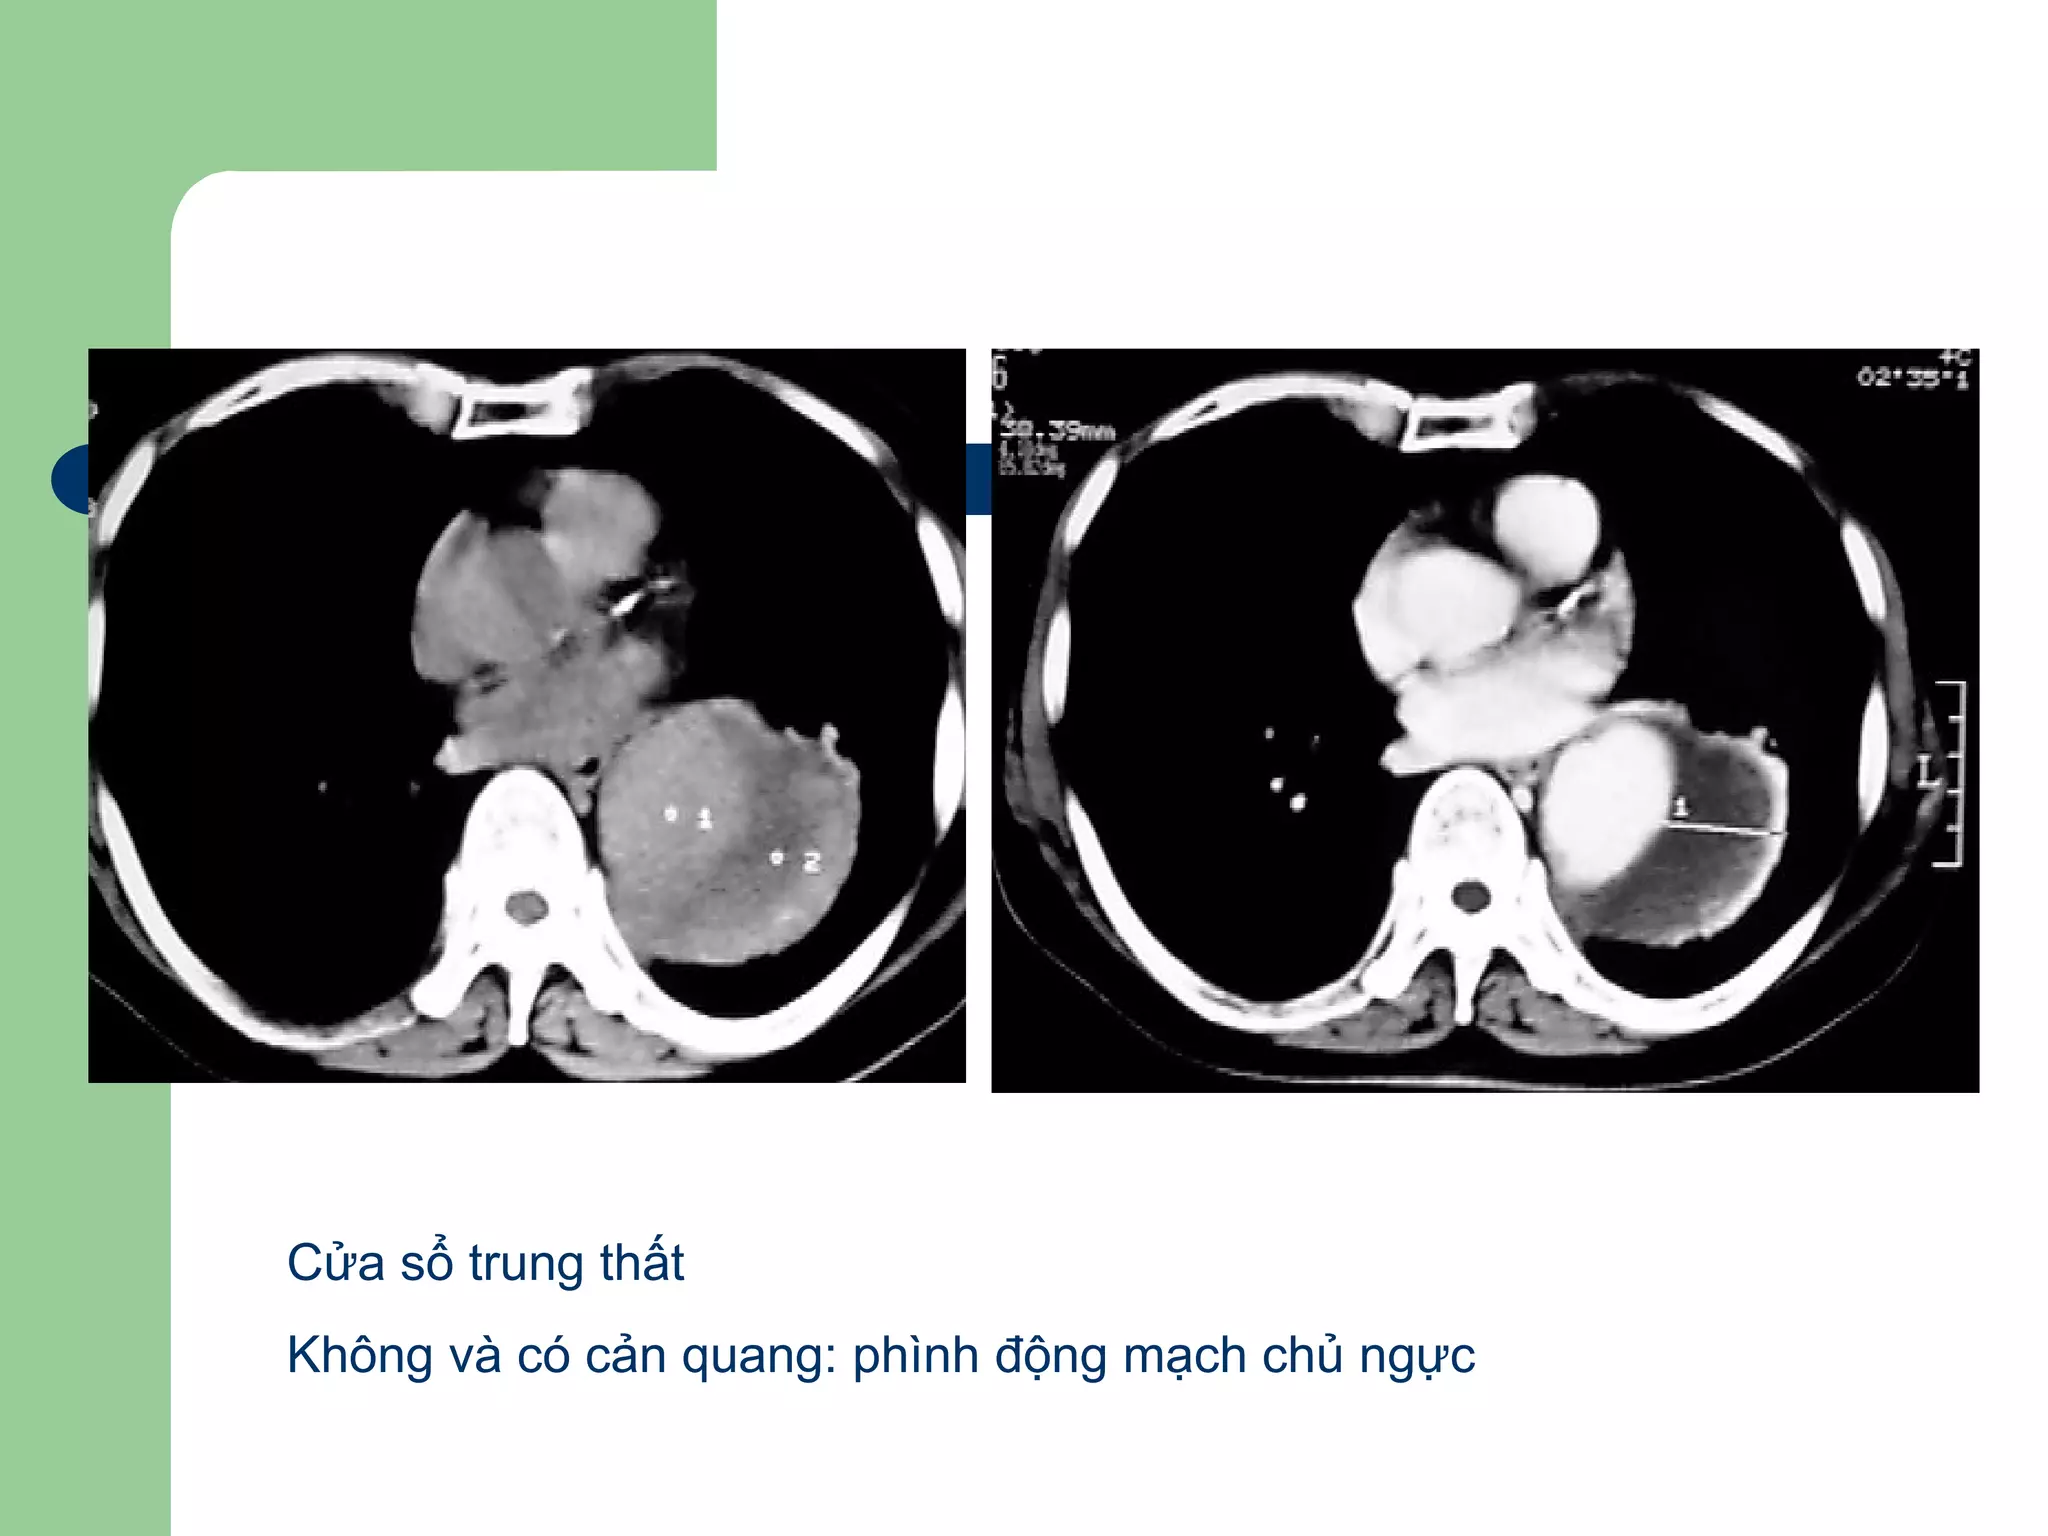

Cửa sổ trung thất

Không và có cản quang: phình động mạch chủ ngực

Phình động mạch chủ ngực

 Hình ảnh CT: lớn khẩu kính động mạch (>4-

5 cm), huyết khối trong lòng, đóng vôi thành

mạch

Phình động mạch chủ ngực, có

huyết khối

Cửa sổ trungthất Không và có cản quang: phình động mạch chủ ngực

Phình động mạchchủ ngực  Nguyên nhân: Xơ vữa động mạch, chấn thương, bẩm sinh, viêm nhiễm, tăng áp động mạch…  Hình ảnh CT: lớn khẩu kính động mạch (>4- 5 cm), huyết khối trong lòng, đóng vôi thành mạch

Phình động mạchchủ ngực, có huyết khối